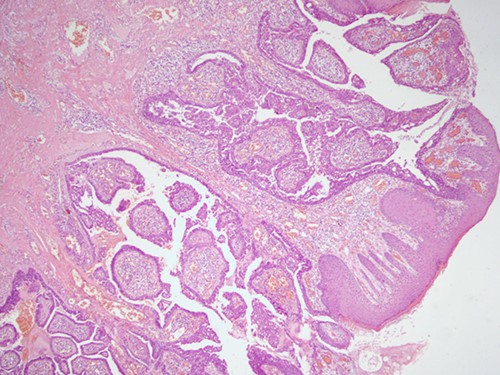

The histopathological examination found cystic invaginations of the infundibular epithelium projecting into the dermis, covered by a double cell layer (Fig. 2), proliferation of glands with prominent papillary architecture (Fig. 3) and fibrous cores containing numerous stromal plasma cells (Fig. 4). Other findings include verrucous (papillomatous) epidermal hyperplasia with hyperkeratosis and hypergranulosis (Fig. 5), irregular duct-like structures and cystic spaces (Fig. 6) and glands with double layer of cuboidal columnar epithelium and numerous stromal plasma cells (Fig. 7). These findings are compatible with Syringocystadenoma papilliferum with no signs of malignancy.

H&E staining, 4× magnification. Cystic invaginations of the infundibular epithelium projecting into the dermis, covered by a double cell layer.